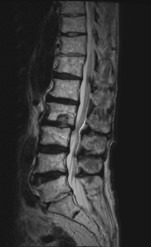

腰で多い病気

• 変形性腰椎症

• 腰椎圧迫骨折

• 腰椎椎間板ヘルニア

• 腰部脊柱管狭窄症

腰痛、お尻からふくらはぎに至る痛み(坐骨神経痛)やしびれ感、間欠跛行(歩くと足に痛みやだるさが生じ、長い距離を歩けなくなる。腰を曲げて休むとおさまる)、膀胱直腸障害(尿の回数が多い)等の症状を伴います。その他、背骨の腫瘍や炎症等も扱います。

治療について

受診された際には問診、診察を行い、画像検査(レントゲン、MRI、CT)や採血検査を行い、診断を付け、治療方針を説明します。 上記のような保存治療を行っても取れない痛みや、手の使いにくさや歩行困難、排尿排便障害などが出現し症状が進行性の場合は手術加療が必要となります。

• 腰椎椎弓切除術

適応となる疾患

腰部脊柱管狭窄症

骨を削って靭帯を切除する除圧術のみで加療可能な患者さんに受けていただく手術です。

• 腰椎後方固定術

腰椎椎間板ヘルニア、変形性腰椎症、腰椎(分離)すべり症など

骨を削って靭帯を切除する除圧術のみで神経症状の改善が困難と判断された場合は、固定術も行います。

• ヘルニア摘出術

腰椎椎間板ヘルニア

痛みやしびれ、足の筋力低下などが薬物療法やリハビリテーションなど保存的治療でも改善しない場合、ヘルニア摘出術を行います。